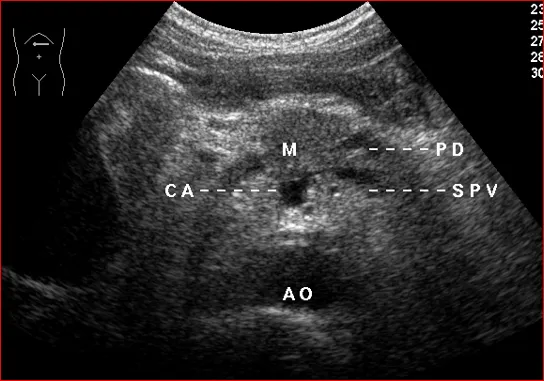

利用标识血管来判断胰腺的位置

胰腺-长轴切面

胰体-纵切扫查